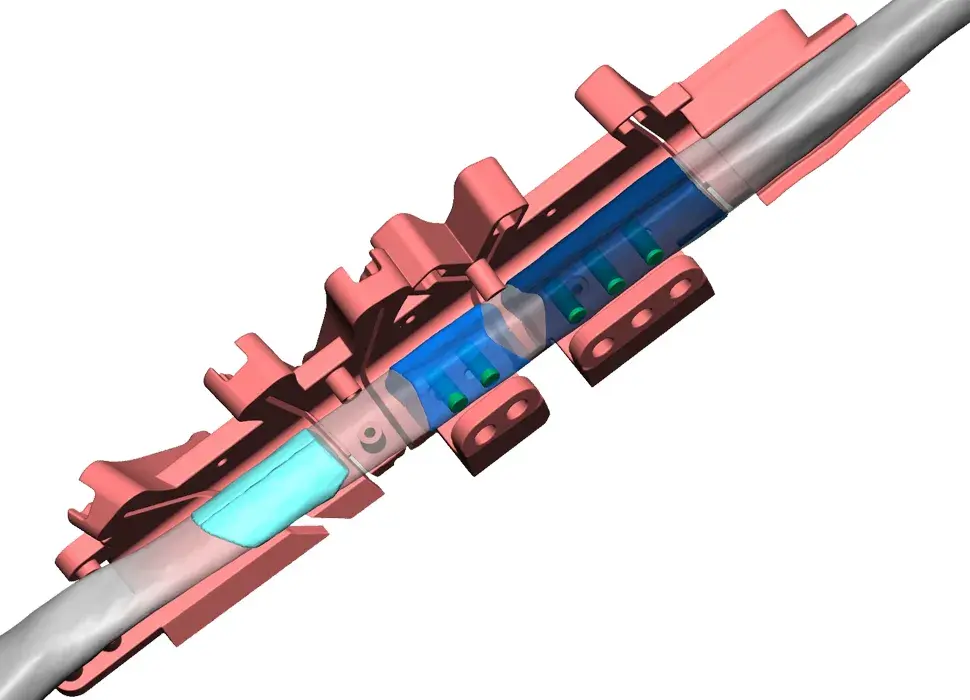

3D Systems' VSP® surgical planning solutions for craniomaxillofacial (CMF) applications received FDA clearance as a service-based approach to personalized surgery over 10 years ago.

3D Systems and Stryker Corporation have partnered to provide surgeons with best-in-class products and services for craniomaxillofacial surgeries. As a leader in personalized healthcare solutions, 3D Systems has planned and delivered devices for more than 140,000 patient-specific cases. The Stryker Craniomaxillofacial business specializes in providing patient-specific options and innovative solutions that help drive efficiencies in surgical suites. The combination of Stryker’s specialized team and advanced implants with 3D Systems' cutting-edge 3D printing technologies and expert consulting services positions both companies to provide a superior level of service to healthcare professionals who use these revolutionary solutions.